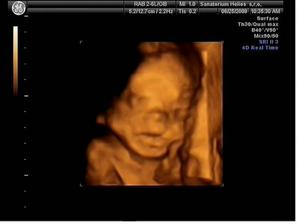

25.6.2009 (24 tt) máme za sebou krásný 3D/4D ultrazvuk v Heliosu. Vše je tak, jak má být :o) A máme definitivně potvrzený pohlaví - je to KLUK - tatínek má důvod k radosti :o) Mimi má 565 g, měří mezi 25 a 30 cm.